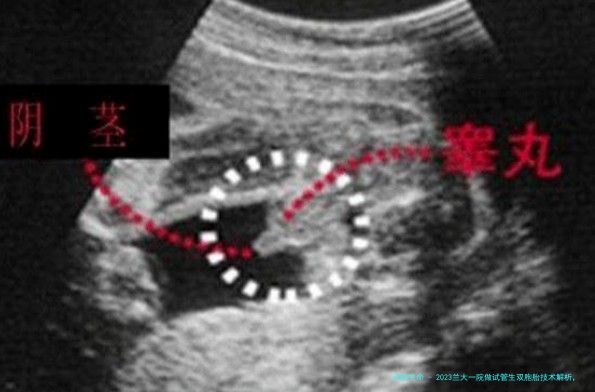

在试管过程中,要是患者夫妇两方的身体条件都满足相关要求,如此医院是能够为病患移植2枚胚胎的,而如果移植到子宫内的2枚胚胎都成功着床了,那么即是通过试管技术怀上了一双孪生儿。但是做试管双生子其实不是百分之百安全的,有可能在试管过程中出现以下风险: